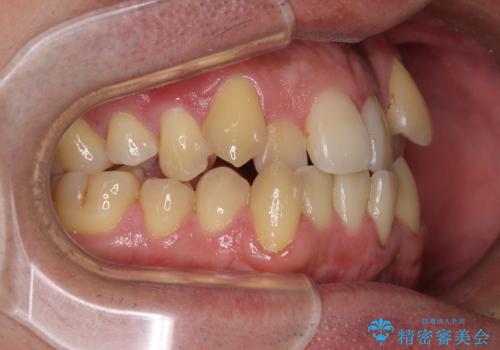

クロスバイトは、治療の過程で咬み合わせが大きく変化する期間があり、食事が取りにくくなってしまいます。

また、装置が対合歯と咬み合ってしまい、頻繁に脱落するなど、色々と面倒なことがあり、治療がスムーズに進まないことがあります。